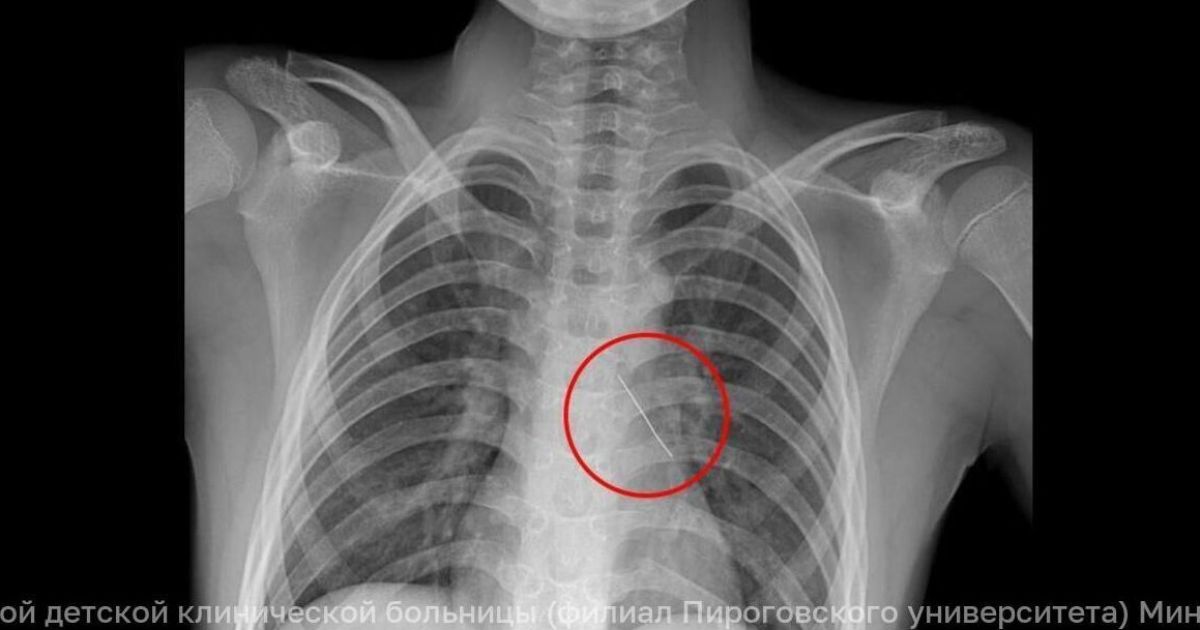

Острый металлический предмет попал в нижнюю долю левого бронха и пробил его насквозь. Ребенка экстренно отправили в Москву — в Российскую детскую клиническую больницу, где торакальные хирурги боролись за его легкое.

В Москву мальчик поступил в тяжелом состоянии. Говорить мог только шепотом, жаловался на дикую боль в груди. Снимок подтвердил худшее: инородное тело глубоко засело в бронхе и повредило стенку. Заведующий отделением реконструктивной и восстановительной хирургии грудной полости РДКБ Евгений Андреев пояснил: такая травма может привести к попаданию воздуха в плевральную полость, сдавлению и даже коллапсу легкого. Помощь требовалась немедленно.

Хирурги решили не делать открытую операцию. Через эндоскоп они зашли в левый главный бронх, убрали скопившуюся мокроту и увидели булавку. Она была изогнута и острым концом торчала прямо в ткани. Под визуальным контролем специальными оптическими щипцами инструмент аккуратно извлекли, стараясь не допустить сильного кровотечения.

Контрольный рентген показал: воздух в грудную полость не попал, легкое цело. Операция прошла успешно. Через три дня мальчика уже выписали — под наблюдение калининградских врачей. Из больницы он ушел своими ногами.